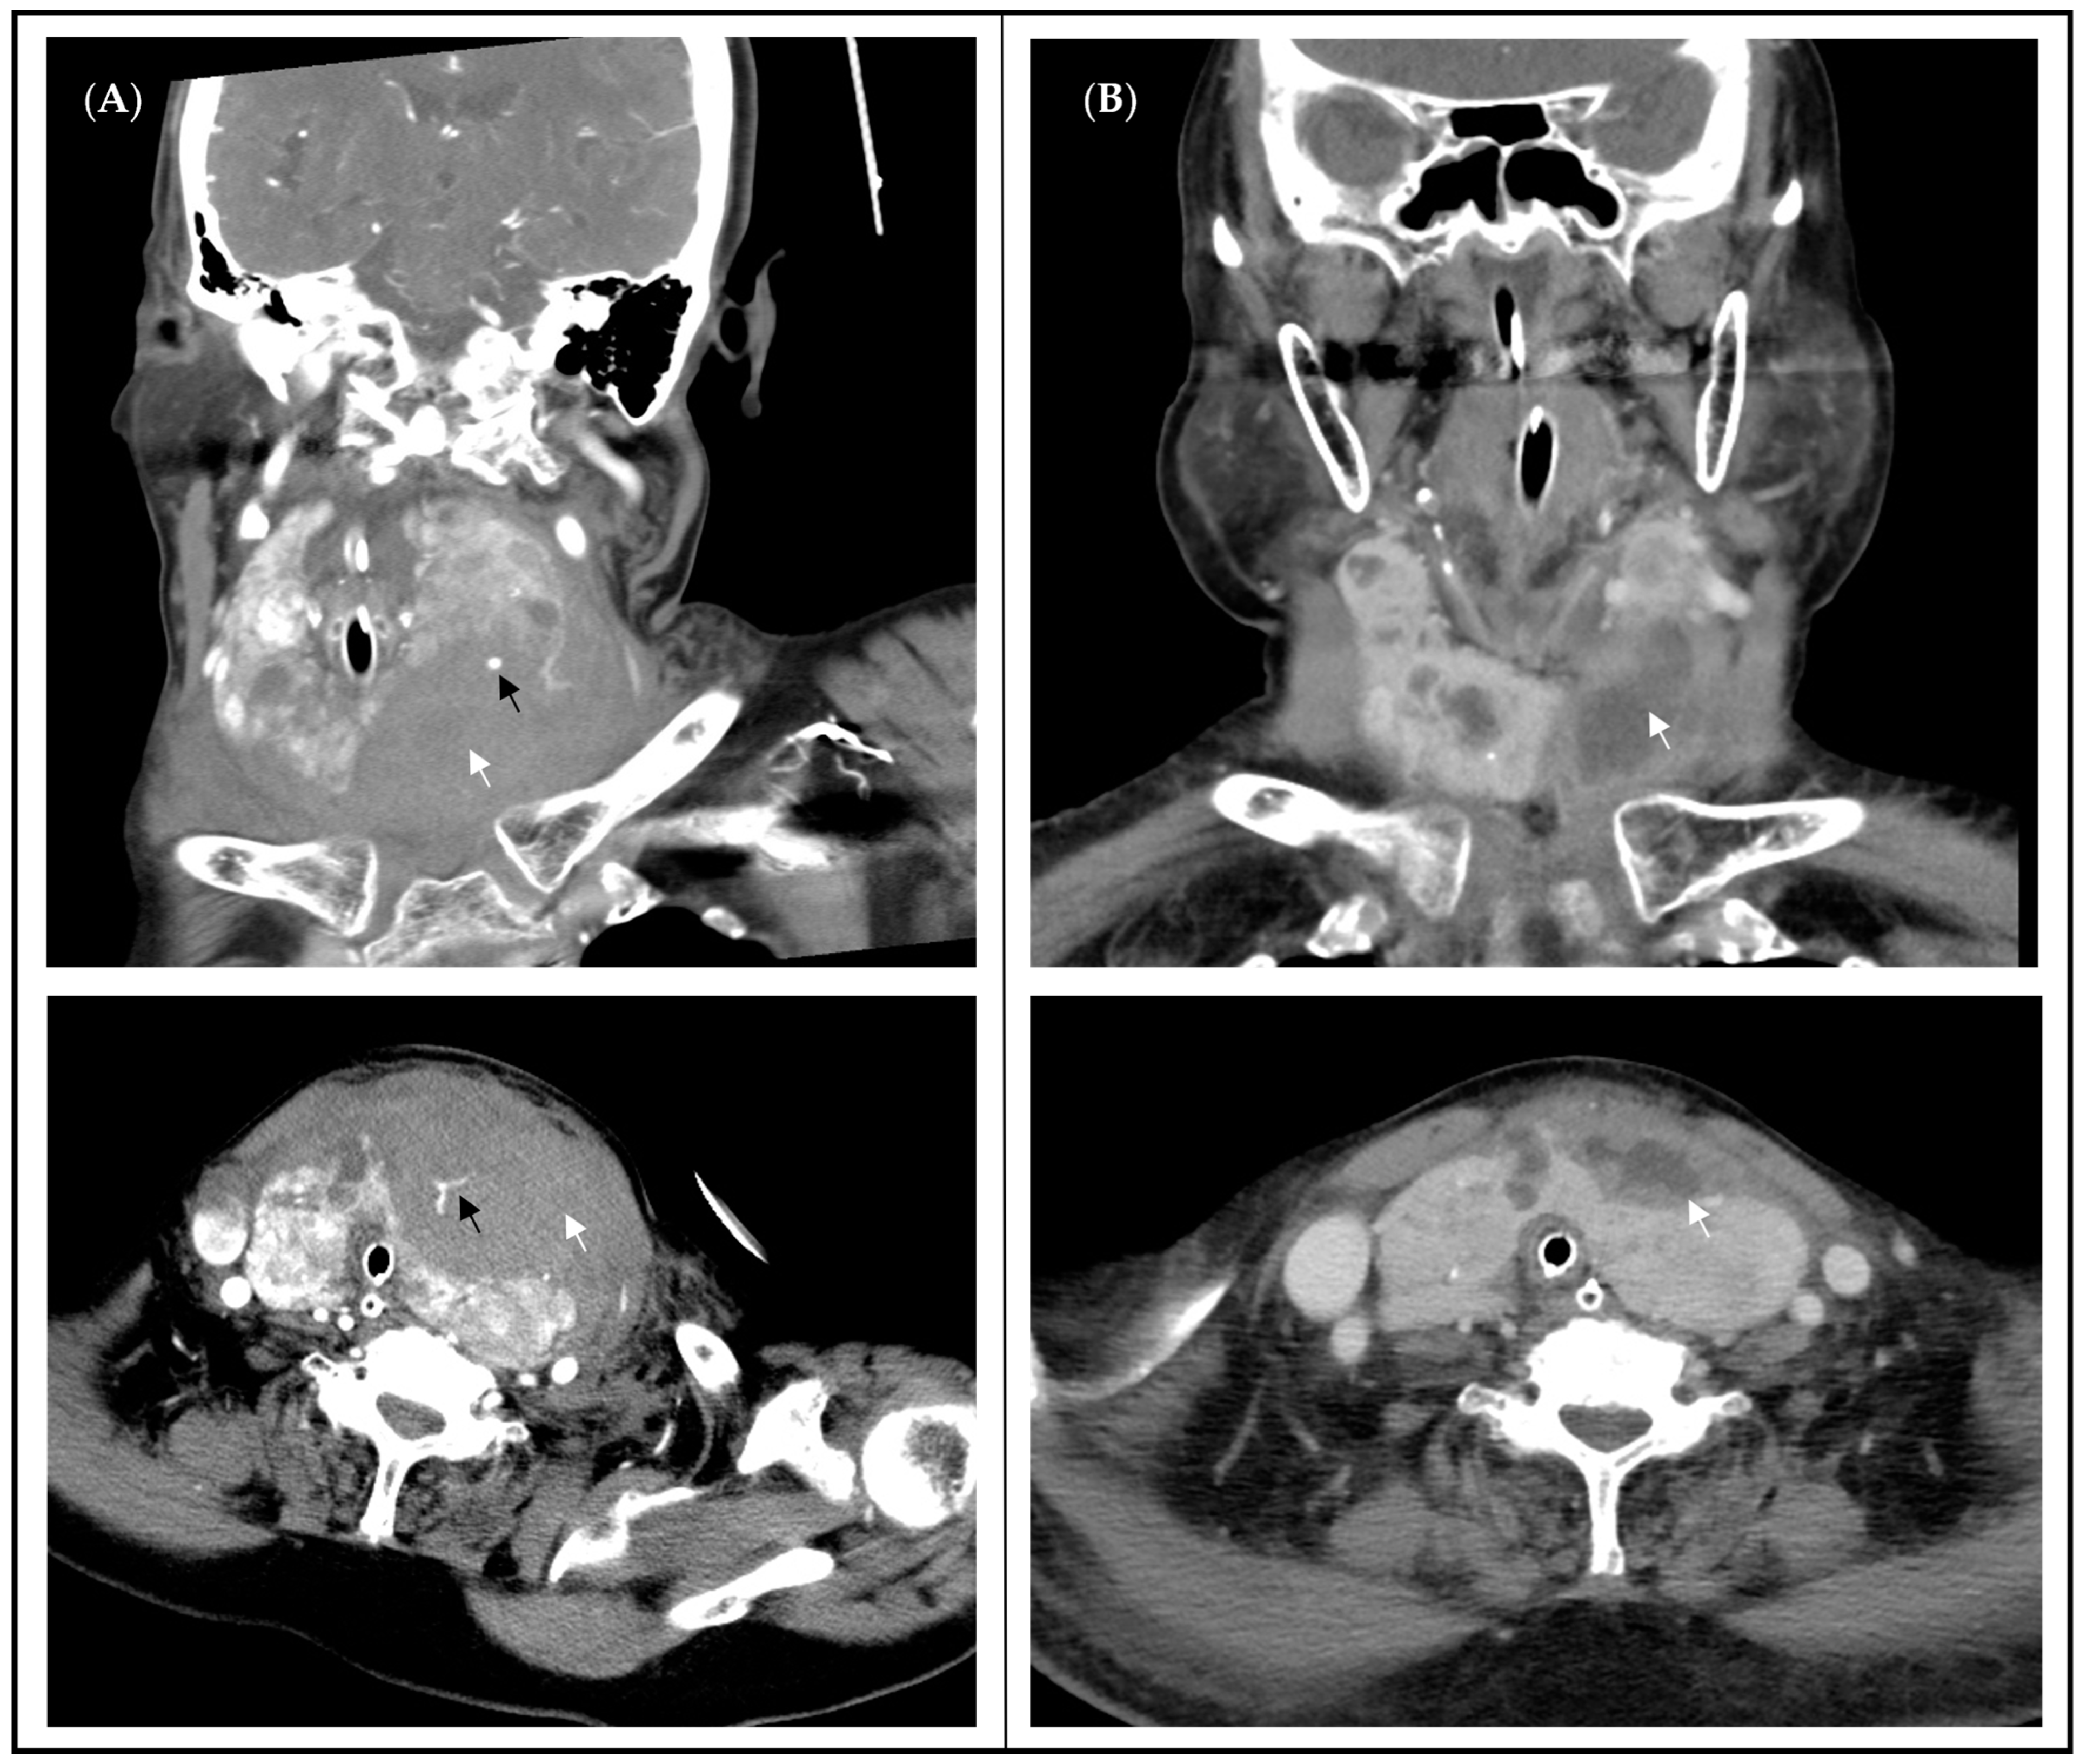

3.3.1. Case 1

| 1 | 98 | F | independent | DM, HTN, CKD, Hyperthyroidism | 0.2 | Hematoma after FNAC caused respiratory failure | Endocrinologists | Non-diagnostic | Left thyroidectomy | 270 | nil | 15 * | 19 ǝ |

| 2 | 92 | F | dependent | HTN | 0.2 | Rapid progression of neck mass with skin ulceration | Endocrinologists | Squamous cell carcinoma | Total thyroidectomy + PMMC flap | 350 | Transient hypocalcemia | 13 * | 28 ǝ |

| 2 | 92 | F | poorly to undifferentiated carcinoma with prominent squamous differentiation, bilateral | Follicular neoplasm of uncertain malignant potential, left | 10.6 | 8 | 510 | 227.8 | Unifocal | nil | nil | nil | Present |

| 3 | 90 | M | Hürthle cell carcinoma, left | Nodular goiter, right | 9.3 | 9 | 130 | 206.0 | Unifocal | nil | nil | nil | nil |